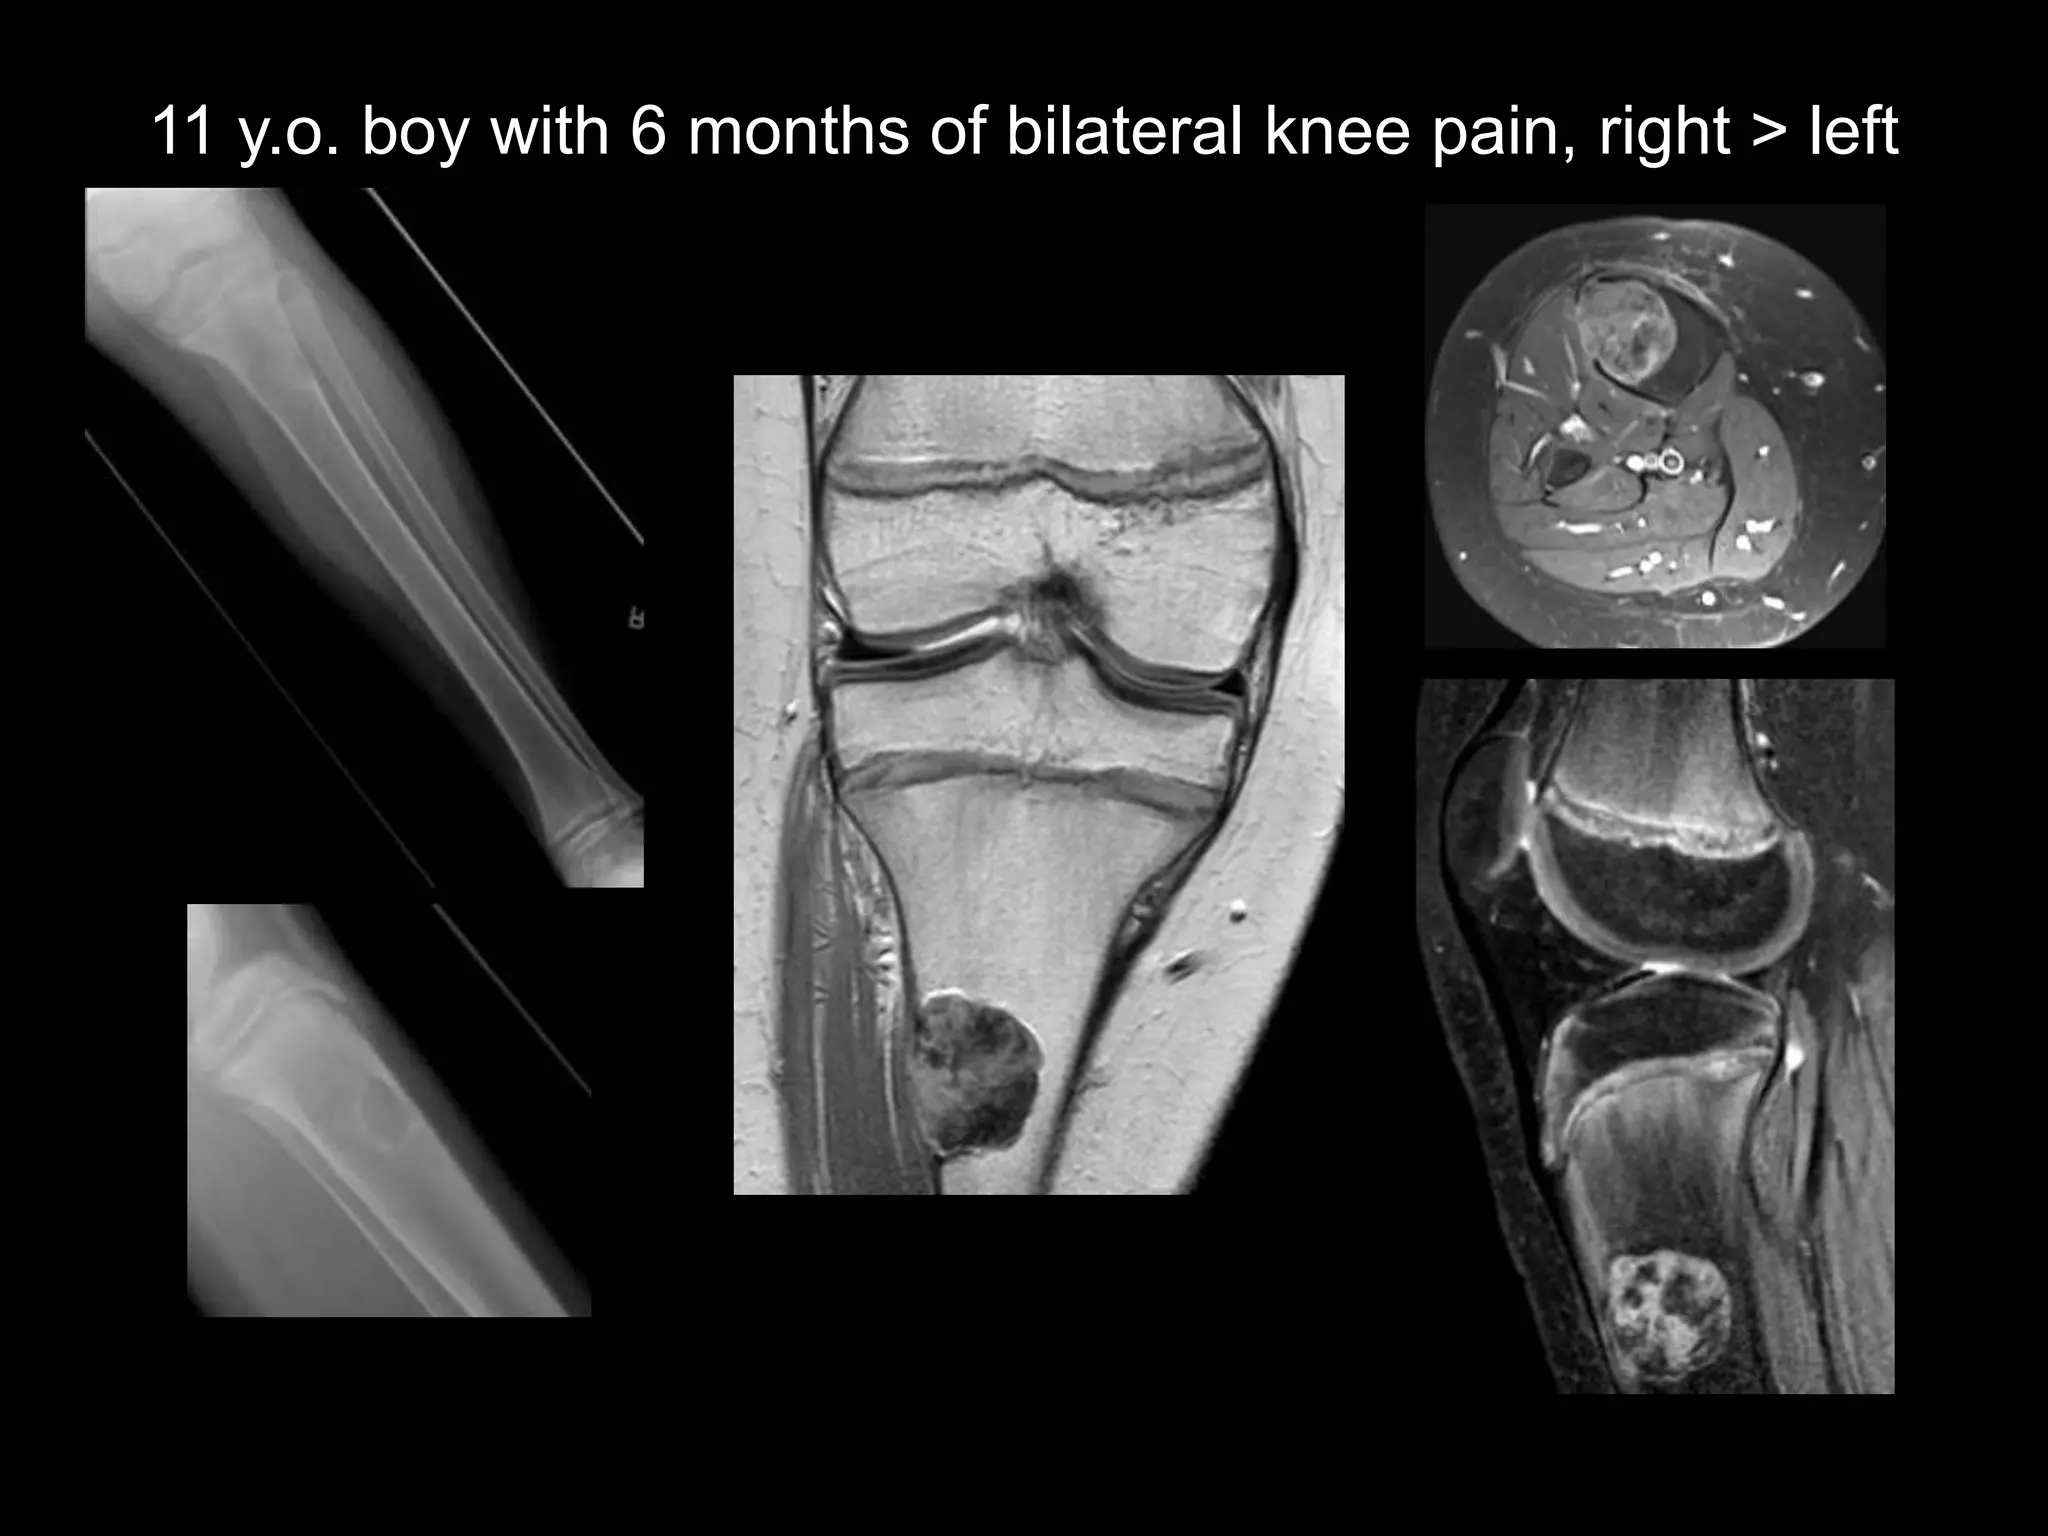

11 y.o. boy with 6 months of bilateral knee pain, right > left

Findings

• Benign appearing tibial metaphyseal lesion

– Vascular (enhancement)

– No marrow edema or soft tissue mass

– Cortically based, sclerotic margins

• Systemic physeal widening

– Faint ZPC

– Metaphyseal fraying, osteopenia

Phosphaturic mesenchymal tumor

(PMT) with oncogenic osteomalacia

• Benign mesenchymal neoplasm

• Secretes phosphatonin (FGF 23)

– Inhibits renal phosphate reabsorption and conversion of

25-hydroxyvitamin D > 1,25 dihydroxyvitamin D

– Result is osteomalacia (rickets)- paraneoplastic

syndrome

• Tumor locations: extremities, facial bones

PMT with osteomalacia

• Labs

– low serum phosphate, normal

calcium

– high 25-hydroxyvitamin D, low

1,25 dihydroxyvitamin D

– elevated FGF 23

• Imaging: Whole Body MR for

occult lesions

• RX: surgical resection (FGF

levels normalize in 1wk)